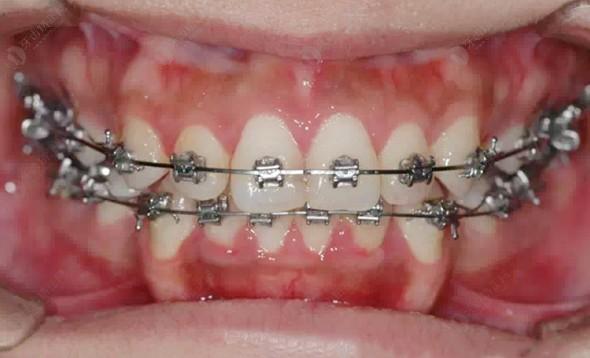

避免牙弓擴(kuò)展對牙周組織造成損傷